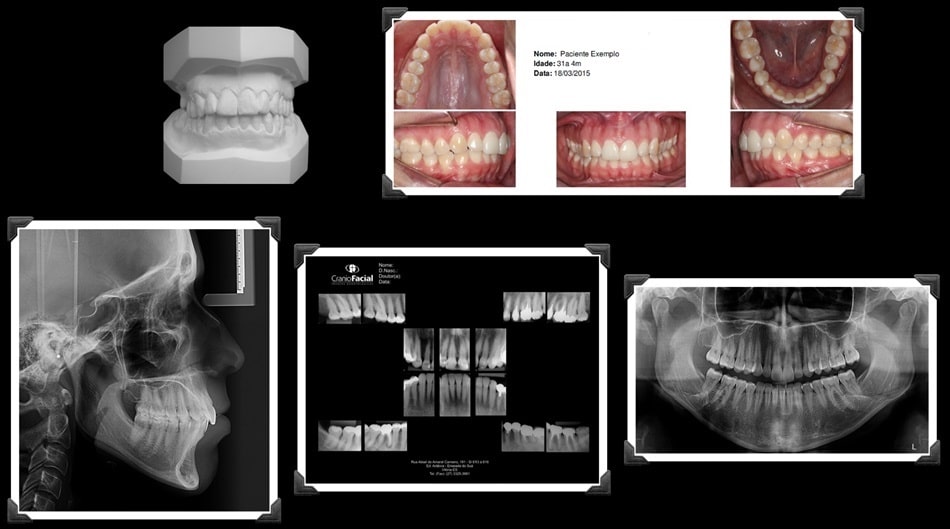

RADIOGRAFIAS DIGITAIS

Radiografia Panorâmica

Telerradiografia Lateral / Frontal

Radiografias Periapicais

DOCUMENTAÇÃO ORTODÔNTICA

Laudos e Análises Cefalométricas

Modelos de Estudo

Fotografias Extra e Intra Bucais